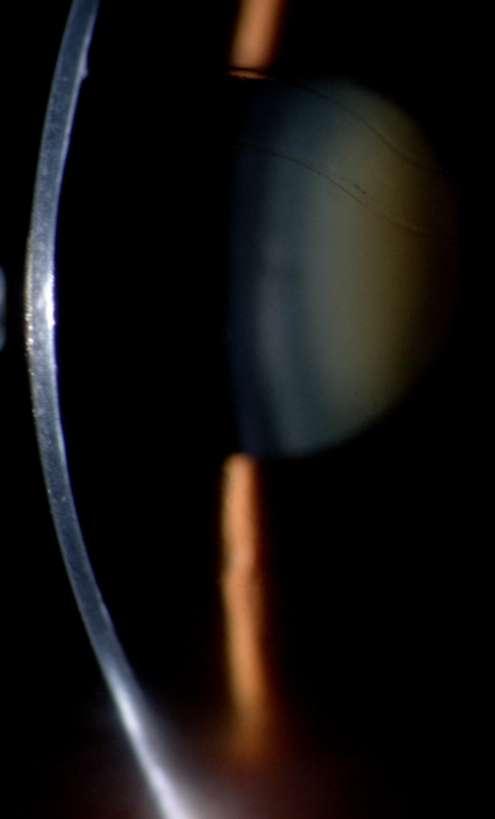

7.B. CATARATA LAMELAR

Imágenes aportadas por Dr. Álvaro Rodriguez

BAü La catarata lamelar también denominada zonular, es la más frecuente de las cataratas infantiles.

ü Se puede heredar en forma autosómica dominante.

ü Se presentan como opacidades bilaterales del núcleo y son el resultado de un daño al cristalino durante el desarrollo fetal siendo las capas más internas afectadas en mayor importancia mientras más precoz haya sido el daño.

ü Clínicamente se caracteriza por la presencia de opacidades en el cristalino que semejan protuberancias en forma de dedos proyectánddose a partir de un núcleo opacificado asociada con regiones de opacidad pulverulenta (Imagen A y B).

Messina O, González L, Cuevas S. Espectro clínico en una familia con catarata lamelar autosómica dominante. Rev Mex Oftalmol; Mayo-Junio 2005; 79(3): 163-165.